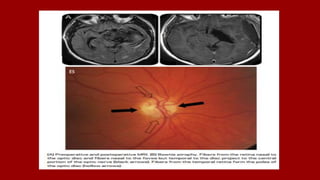

• The central retinal artery along with vein

crosses the subarachnoid space to enter the

nerve on its inferomedial aspect.